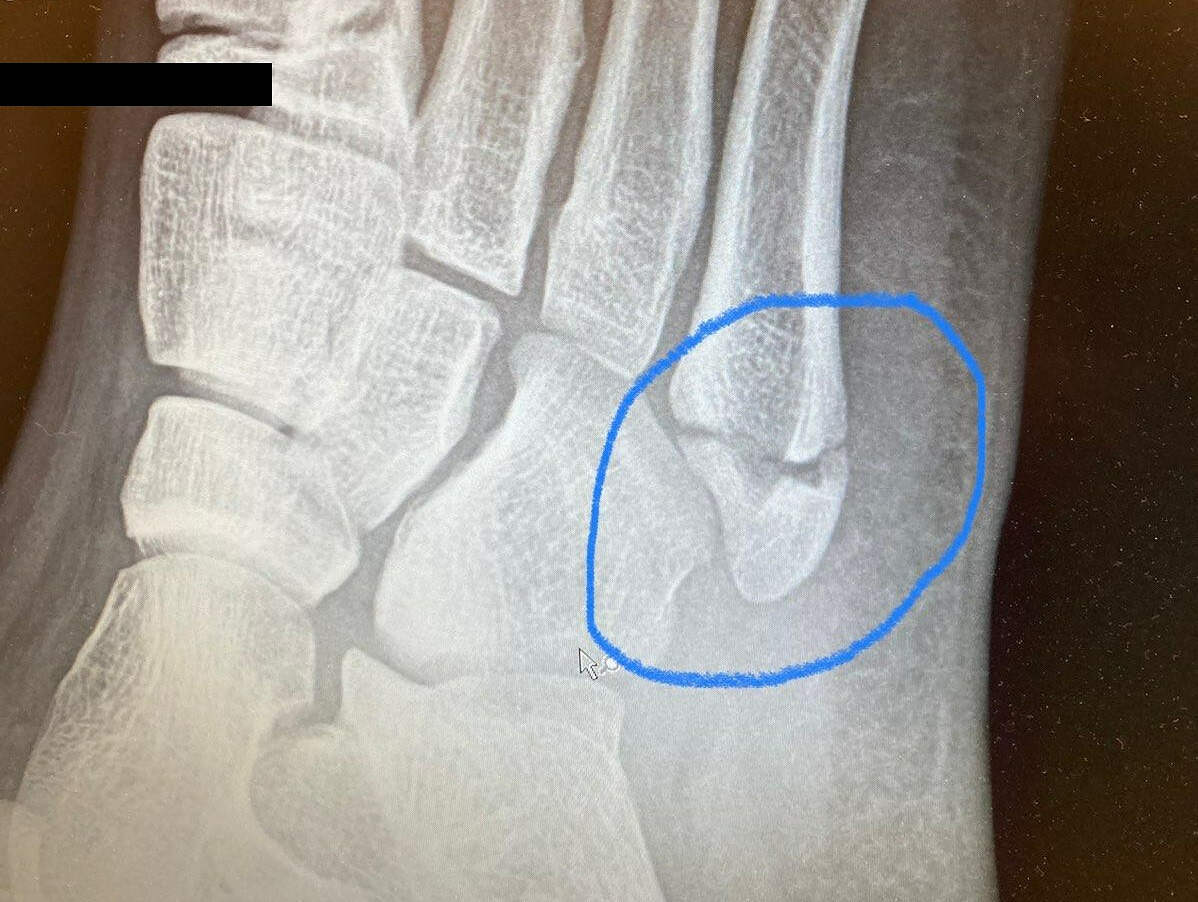

My kid was running around on a hiking path on Sunday and broke a bone in his foot. It’s the long bone that runs from about midfoot to the pinky toe. The break is close to the end that’s further from the toe.

He’s in a boot and on crutches. My wife thinks he ought to have one of those wheelie cart things, but he is resistant and wants to stick to crutches. The doctor said to not bear any weight on the foot whatsoever until we can X-ray again in a few weeks and reassess.

He has either a tuberosity avulsion fracture of the 5th MT or a Jones fx at the junction of metaphysis and diaphysis. The former is more common and sounds like what you are dealing with. A CAM walker is treatment of choice, with followup to evaluate for non union (can be a problem in this location due to tenuous blood supply). Jones fx has best outcome with immediate screw fixation but they can heal spontaneously as well.

I agree with the CAM walker and no weight bearing until assessment in a few weeks.

Here’s the break:

Yup, that’s a tuberosity avulsion fx.

it was the weirdest thing. He’s run dozens of miles the last few months and was just running down a path in the woods. I don’t think there was a root or a rock or anything, he was just rounding a corner and it rolled.